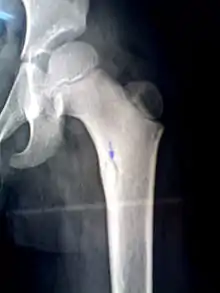

Рентген бедренной кости ребенка показывает костный секвестр (указан синей стрелкой).